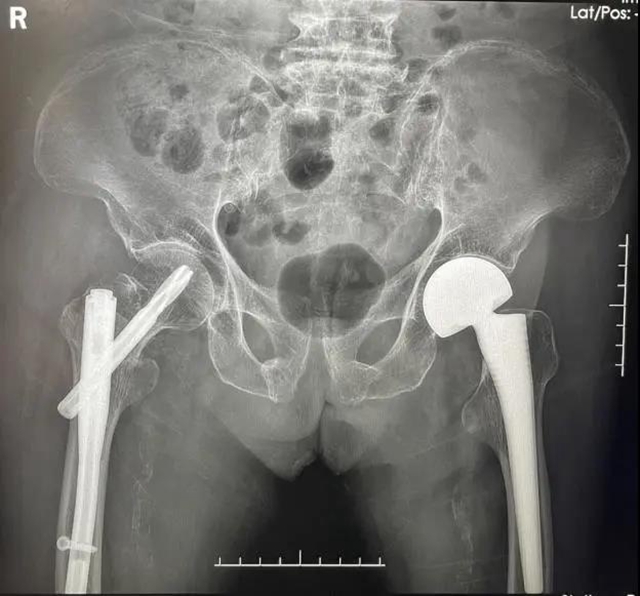

第二次手术,术前X片检查

第二次手术,术后X片检查

不幸的是,何婆婆出院不足1月,在家自行上厕所时再次不慎跌倒,导致右侧髋部疼痛、活动受限,于我院检查后确诊为右侧粗隆间骨折。

面对1个月内的第二次髋部骨折,骨与关节外科再次采用MDT模式迅速评估了老人的身体状况后,谭美云教授建议手术治疗,避免卧床造成更严重的后果。

在得到了老人和家属的共同认可后,在多学科合作的支持和加速康复理念的指导下,谭美云教授团队于患者入院后48小时内采用微创手术方法,进行了右股骨粗隆间骨折闭合复位髓内钉内固定手术。

术后早期拔除尿管,指导患者床上进行肢体主动功能锻炼,实现早期康复,术后第3天何婆婆就可以完全卧床自主活动,轮椅辅助下外出活动,并尝试着下地站立,于术后第5天康复出院。